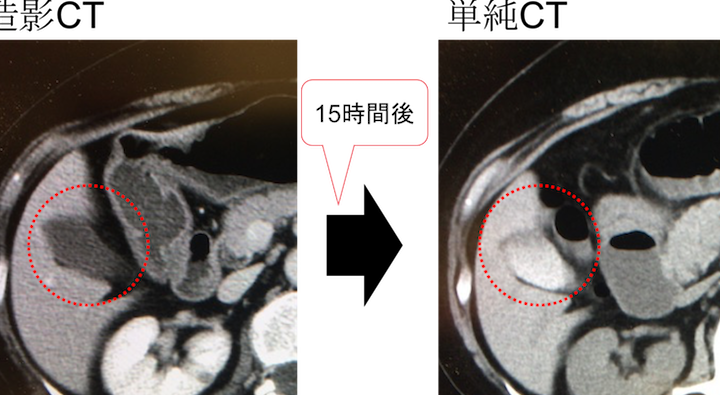

造影剤使用後の腎機能回復

造影剤使用後の腎機能回復は、患者の状態に大きく依存します。腎機能の状態や、使用した造影剤の種類によって、回復の速度は異なるため、適切な対応が必要です。

回復にかかる時間

腎機能の回復にかかる時間はケースバイケースです。一般的には、健康な腎機能を持つ患者では、造影剤使用後数日から数週間で回復が見られます。以下のような要因が影響します。

造影剤使用後の腎機能低下についての考察は、患者の健康管理に不可欠です。腎機能が低下している患者においては、造影剤投与の影響が強く出るため、事前の評価が重要だとされます。

腎機能の回復期間は、患者ごとに異なる。一般的に、健康な腎機能を持つ患者では、数日から数週間以内に回復が見られることが多いです。しかし、慢性腎疾患を有する患者の場合、回復にはより長い時間がかかることがあります。このため、回復の確認と適切な管理が不可欠です。